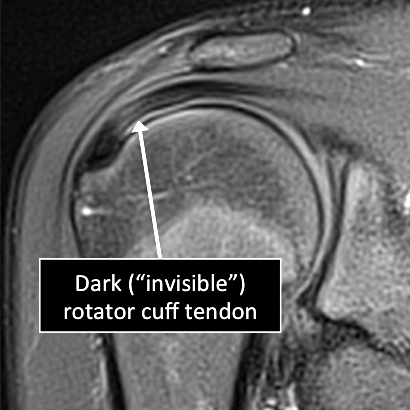

- In the shoulder, as in many other parts of the body there are certain structures that can’t be seen (they look black or dark) with the standard MRI.

- There are new “software” programs that allow us to see structures with different contrast (bright versus dark).

- Some of these “invisible” or dark structures are unique to the shoulder (glenoid labrum) and others are found in other parts of the body (e.g. cartilage, ligaments, tendons, cortical bone).